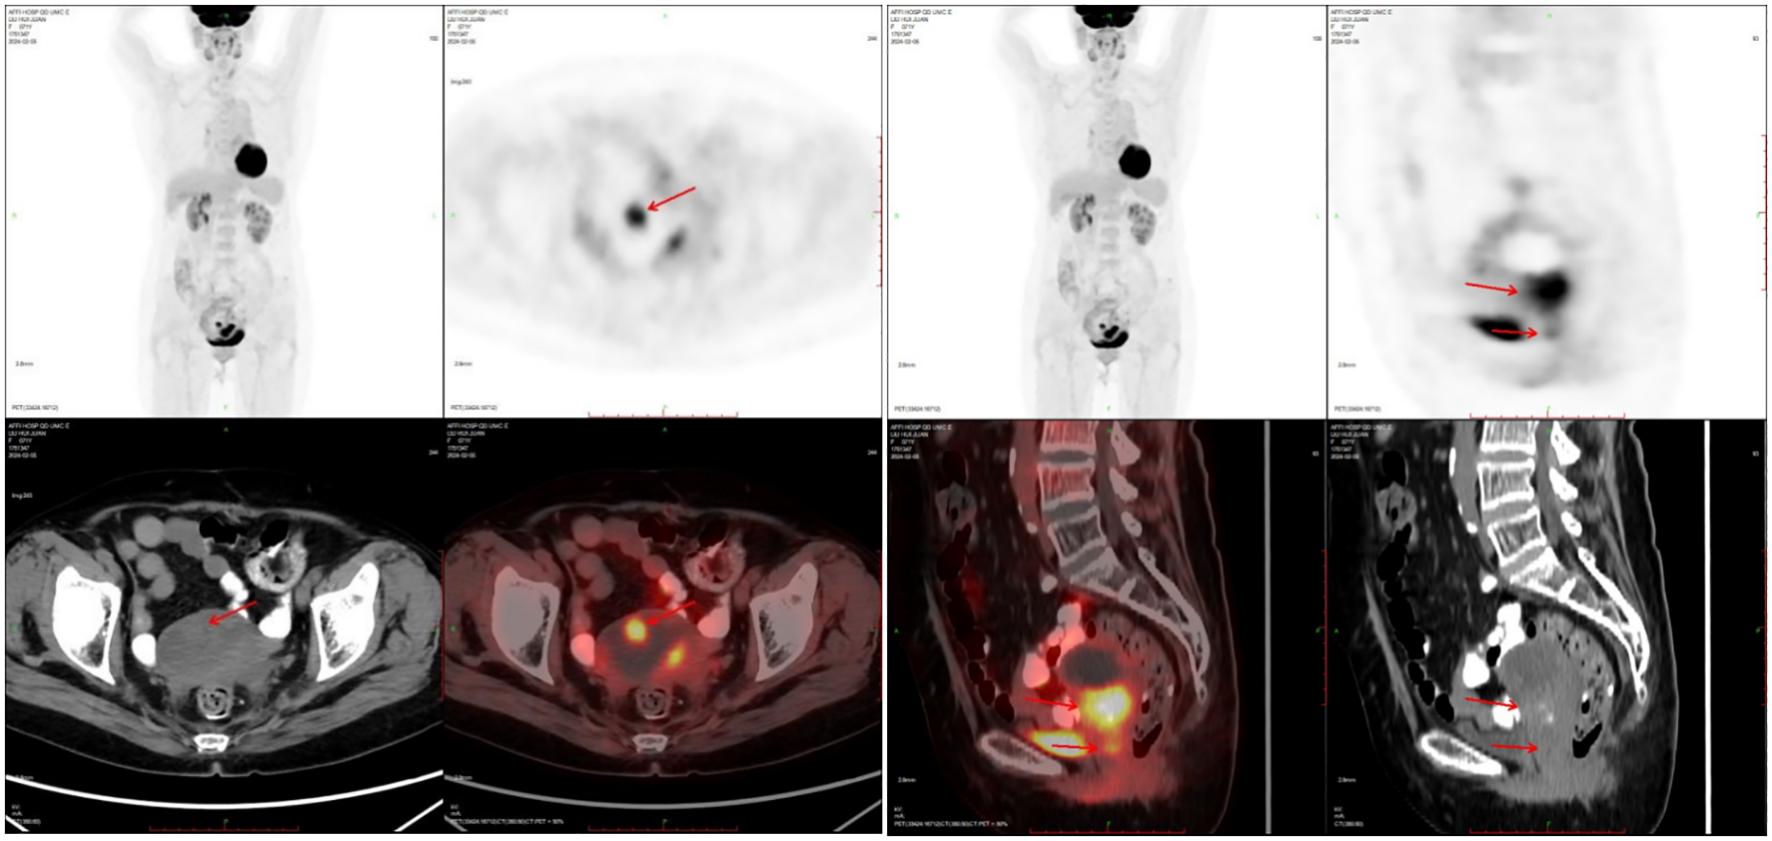

A 71-year-old postmenopausal woman presented with scant dark-red vaginal bleeding. She sought medical treatment at Qingdao University Affiliated Hospital. B-ultrasound revealed an enhanced echo in the lower uterine segment, measuring approximately 5.6×4.8×3.8 cm, raising suspicion of endometrial carcinoma (Figure 1). Diagnostic endometrial biopsy subsequently confirmed adenocarcinoma, favoring endometrioid subtype. Serum tumor markers were as follows: Alpha-fetoprotein (AFP) 15.480 ng/mL (reference range: 0–7 ng/mL), carcinoembryonic antigen (CEA) 8.070 ng/mL (reference range: 0–5 ng/mL), carbohydrate antigen 199 (CA199) 98.280 U/mL (reference range: 0–30 U/mL), and carbohydrate antigen 125 (CA125) 8.080 U/mL (reference range: 0–25 U/mL). Whole-body PET/CT demonstrated an ill-defined hypermetabolic soft-tissue nodule (SUVmax ≈13.8) in the uterine corpus-cervix junction and an intracavitary protruding nodule (SUVmax ≈9.3) in the fundus, with no enlarged lymph nodes in the bilateral iliac/inguinal regions, consistent with uterine malignancy (Figure 2). Following an initial diagnosis of endometrial malignancy, the patient was admitted to our gynecology department on February 16, 2024, for surgery. Following admission, a comprehensive medical history was documented. The patient is G3P2A1. Fourteen years ago, she underwent surgical treatment for rectal cancer, followed by adjuvant chemoradiotherapy. Regular postoperative surveillance revealed no signs of recurrence. On February 20, 2024, the patient underwent laparoscopic exploration Laparoscopy revealed dense adhesions between the rectum/sigmoid colon and left pelvic wall, with fibrosis impeding vascular dissection. Frozen section pathology indicated moderately-to-poorly differentiated adenocarcinoma with necrosis and calcification, infiltrating nearly the full myometrial thickness. Consequently, we performed laparoscopic extrafascial total hysterectomy, bilateral adnexectomy, right pelvic lymph node dissection, para-aortic lymph node biopsy, and pelvic adhesion lysis.

Figure 1. The ultrasound showed enhanced echo in the lower segment of the uterus, ranging from 5.6×4.8×3.8cm, considering endometrial malignancy.

Figure 2. PET-CT showed nodules of soft tissue density at the base of the uterine body, protruding intrauterine, with increased metabolism, which was consistent with malignant uterine tumors.